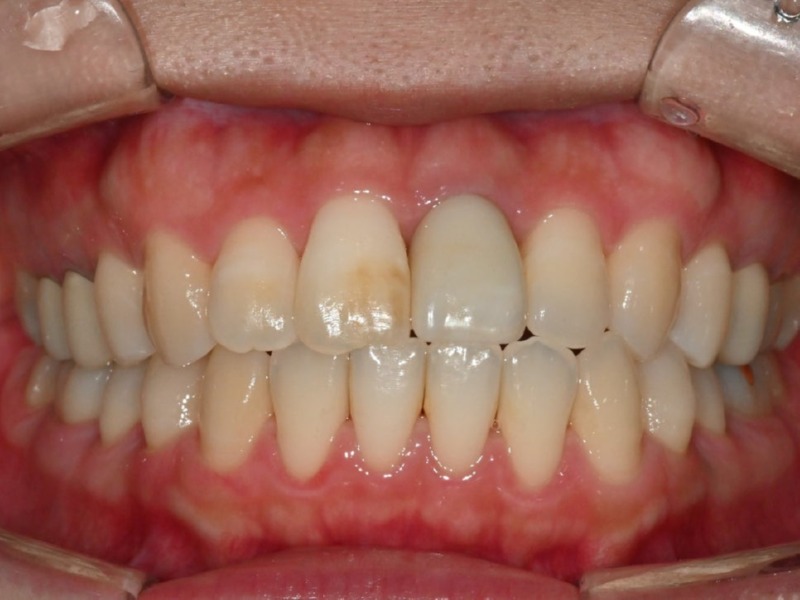

수술 당일 오후, 임시치아를 장착한 모습

수술 2-3시간 후 앞니 임플란트에

고정성 임시치아를 장착한 모습입니다.

수술 직후이기 때문에 봉합사(실)이 있지만,

임시치아임에도 주변 치아와 비교해서

이질감이 거의 없습니다.

틀니 형태가 아니기 때문에

식사 및 발음, 심미적인 기능에서

불편함은 거의 없다고 하셨습니다.

2개월 후, 마찬가지의 디지털 방식으로 스캔하고

제작한 최종 임플란트 치아를 장착할 수 있었습니다.

발치 및 즉시 임플란트 2개월 후